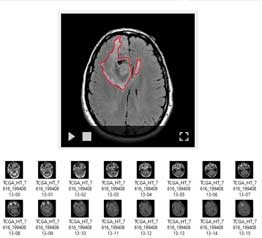

Brain tumour

(MRI scan)

- Automatic tumour detection

- Highlight tumour location

- Show tumour existence